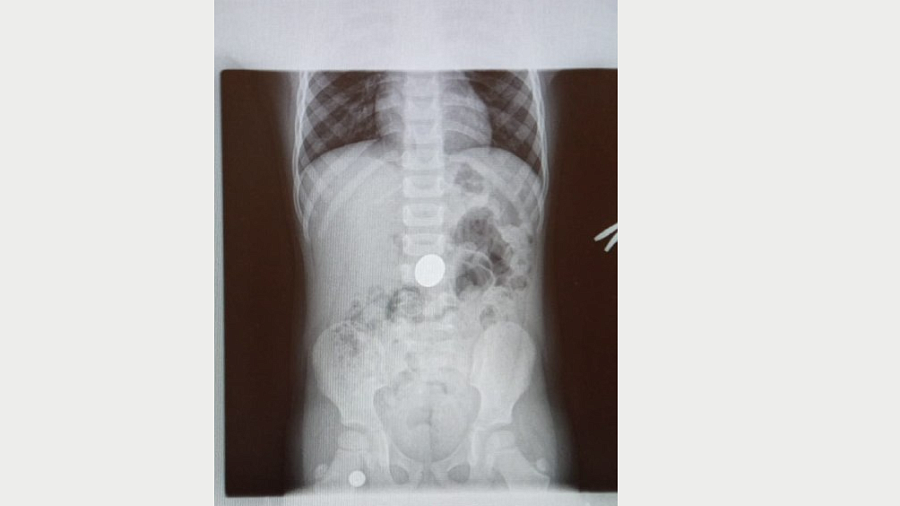

В Туапсинском районе в центральную районную больницу поступил 4-летний мальчик, который проглотил пятирублевую монету.Как рассказал врач-эндоскопист Гор Саакян, маленькому пациенту сразу сделали рентген. Исследование подтвердило, что в желудке ребенка находится инородное тело. Медики приняли решение извлечь объект безоперационным способом.

«Была проведена лечебная гастроскопия под эндотрахеальным наркозом. Монету извлекли, ребенок уже выписан — состояние его здоровья удовлетворительное. Сегодня такие процедуры извлечения инородных предметов, проглоченных пциентами, проводятся на высоком уровне благодаря современному медицинскому оборудованию, которым оснащена ТЦРБ № 1», - рассказал Гор Саакян.